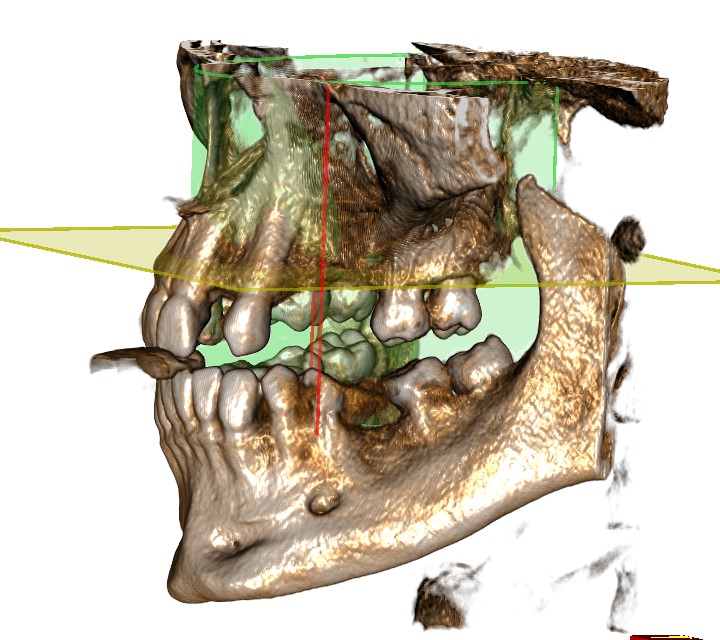

Първи етап.Диагностичен етап – на този етап се изисква от пациентите да имат направен 3D скенер (Може да ни го изпратите предварително). Полученият 3D скенер дава възможност за добра оценка на наличната кост. Скенерът ни помага, прецизно да изчислим точното местоположение на импланта в челюстта, изчисляваме необходимия размер на импланта – височина и ширина.